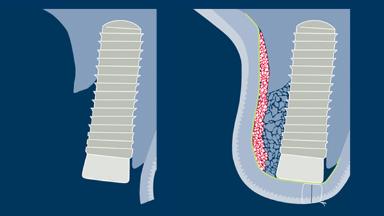

Simultaneous Contour Augmentation Using GBR

- explain the rationale for contour augmentation using guided bone regeneration (GBR)

- list the materials used for contour augmentation in esthetic sites

- describe the treatment concept and surgical steps for simultaneous contour augmentation